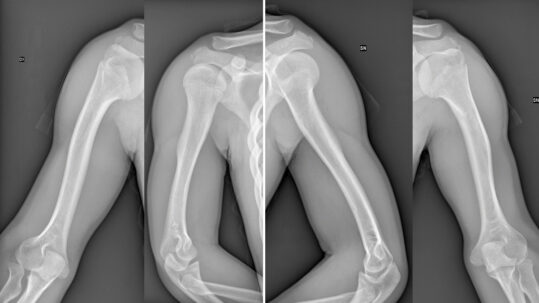

Ipocondroplasia Cure: Allungamento bilaterale delle braccia in bambino

Allungamento bilaterale delle braccia con Ilizarov in bambino con ipocondroplasia: +8 cm e ripresa funzionale completa....